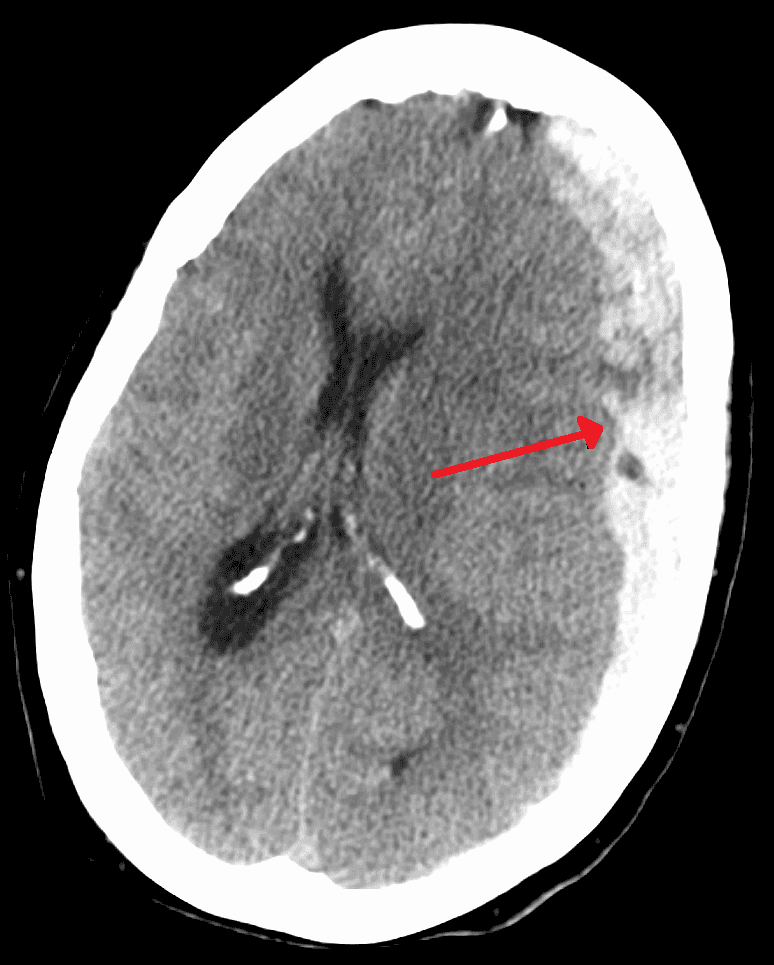

A subdural hematoma (SDH) is a type of bleeding in which a collection of blood—usually but not always associated with a traumatic brain injury—gathers between the inner layer of the dura mater and the arachnoid mater of the meninges surrounding the brain. It usually results from tears in bridging veins that cross the subdural space. Subdural hematomas may cause an increase in the pressure inside the skull, which in turn can cause compression of and damage to delicate brain tissue. Acute subdural hematomas are often life-threatening. Chronic subdural hematomas have a better prognosis if properly managed. In contrast, epidural hematomas are usually caused by tears in arteries, resulting in a build-up of blood between the dura mater and the skull. The third type of brain hemorrhage, known as a subarachnoid hemorrhage (SAH), causes bleeding into the subarachnoid space between the arachnoid mater and the pia mater. SAH are often seen in trauma settings, or after rupture of intracranial aneurysms. TOC The symptoms of a subdural hematoma have a slower onset than those of epidural hematomas because the lower-pressure veins involved bleed more slowly than arteries. Signs and symptoms of acute hematomas may appear in minutes, if not immediately, but can also be delayed as much as two weeks. Symptoms of chronic subdural hematomas are usually delayed more than three weeks after Injury. If the bleeds are large enough to put pressure on the brain, signs of increased intracranial pressure or brain damage will be present. Other symptoms of subdural hematoma can include any combination of the following: Loss of consciousness or fluctuating levels of consciousness Irritability Seizures Pain Numbness Headache (either constant or fluctuating) Dizziness Disorientation Amnesia Weakness or lethargy Nausea or vomiting Loss of appetite Personality changes Inability to speak or slurred speech Ataxia, or difficulty walking Loss of muscle control Altered breathing patterns Hearing loss or ringing in the ears (tinnitus) Blurred vision Deviated gaze, or abnormal movement of the eyes.